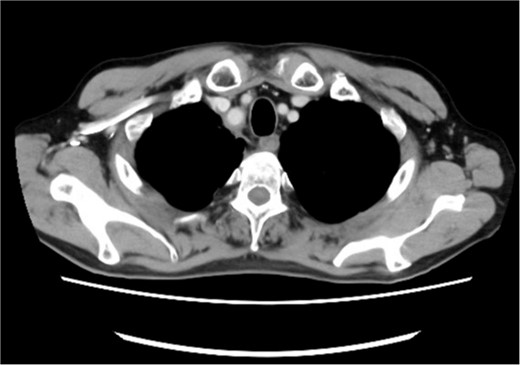

A 72-year-old man diagnosed with NSCLC was referred for possible surgical treatment of a solitary nodule detected in the mesorectum. His medical history included hypertension and endoscopic resection of colonic polyps, with no prior thromboembolism. He had received combined medical treatment for NSCLC (cT4N0M0, stage IIIA) (Fig. 1), including four courses of cisplatin and docetaxel chemotherapy with a 60 Gy/30 fractions radiation dose, followed by 1 year of consolidation therapy with durvalumab (640 mg/body). The patient tolerated the treatment well, achieving a complete response 13 months before presentation (Fig. 2). However, the mesorectal nodule was incidentally discovered during surveillance CT after NSCLC treatment completion. It was round, 15 mm in diameter, showed contrast enhancement, and was near the mesorectal vessels (Fig. 3a and b). An FDG PET/CT scan revealed a solitary mesorectal nodule with an SUVmax of 10.3 (Fig. 4). Consequently, the radiologist suggested differential diagnoses of malignant lymphoma and metastatic lymph nodes from the urinary or lower gastrointestinal tract, as NSCLC typically does not metastasize to mesorectal lymph nodes. No other abnormal FDG uptake was observed. Laboratory tests showed normal levels for tumor markers, including carcinoembryonic antigen, sialyl Lewis X (SLX), squamous cell carcinoma antigen, neuron-specific enolase, cytokeratin fragment (CYFRA), progastrin-releasing peptide, and blood coagulability was within the normal range. Total colonoscopy revealed no neoplastic lesions, and urinary cytology showed nonmalignant urothelial cells. Noninvasive diagnostic approaches, including endoscopic or CT-guided biopsy, were extensively discussed but deemed difficult because of anatomical restrictions, risk of dissemination, and procedure-related complications (such as bleeding or perforation). Because of the potential malignancy and need for en-bloc resection, we opted for surgical resection using a standardized laparoscopically assisted mesorectal excision technique. During rectal dissection, the nodule was not visible through the posterior and lateral sides because it was completely embedded in the mesorectum. Therefore, a Pfannenstiel incision was made in the lower abdomen to exteriorize the rectum after the division of the proximal colon. The nodule was confirmed by direct palpation, marked with a stitch, and subsequently removed after intracorporeal transection of the distal rectum. We inspected the resected specimen and confirmed that the nodule was incorporated (Fig. 5a and b). A colorectal anastomosis was then performed using a double-stapling technique with a circular stapler. The postoperative course was uneventful, except for a slight elevation of the d-dimer level (up to 3.26 μg/ml) on postoperative Day 7, which normalized spontaneously without intensive anticoagulation therapy. The patient was discharged on postoperative Day 10. Pathological examination revealed that the 7-mm white nodule was an intravenous organized thrombus in the mesorectum surrounded by granulation tissue, with no malignancy observed (Fig. 6a and b). Postoperatively, the patient did not require additional chemotherapy or anticoagulation therapy. During the 16-month follow-up, no radiological evidence of NSCLC recurrence and thromboembolism was detected (Fig. 7).

Pretreatment chest computed tomography (CT) image. The arrowheads highlight locally advanced lung cancer invading the chest wall and brachiocephalic trunk (cT4N0M0).